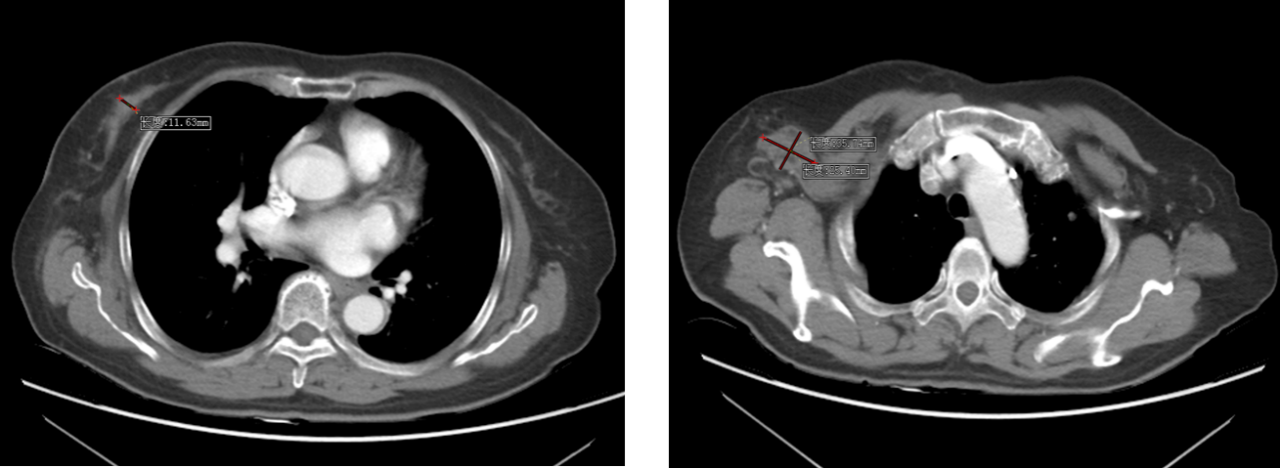

2019 年 10 月乳腺及腋窝淋巴结彩超:右乳 1×1cm 肿块,乳腺彩超提示右乳低回声(BI-RADS 4B 类)、右腋下多发异常淋巴结;穿刺病理示(右乳)浸润性导管癌,免疫组化 ER(-)、PR(-)、HER-2(3+)、Ki-67(+,约 60%);

图1 乳腺及腋窝淋巴结彩超